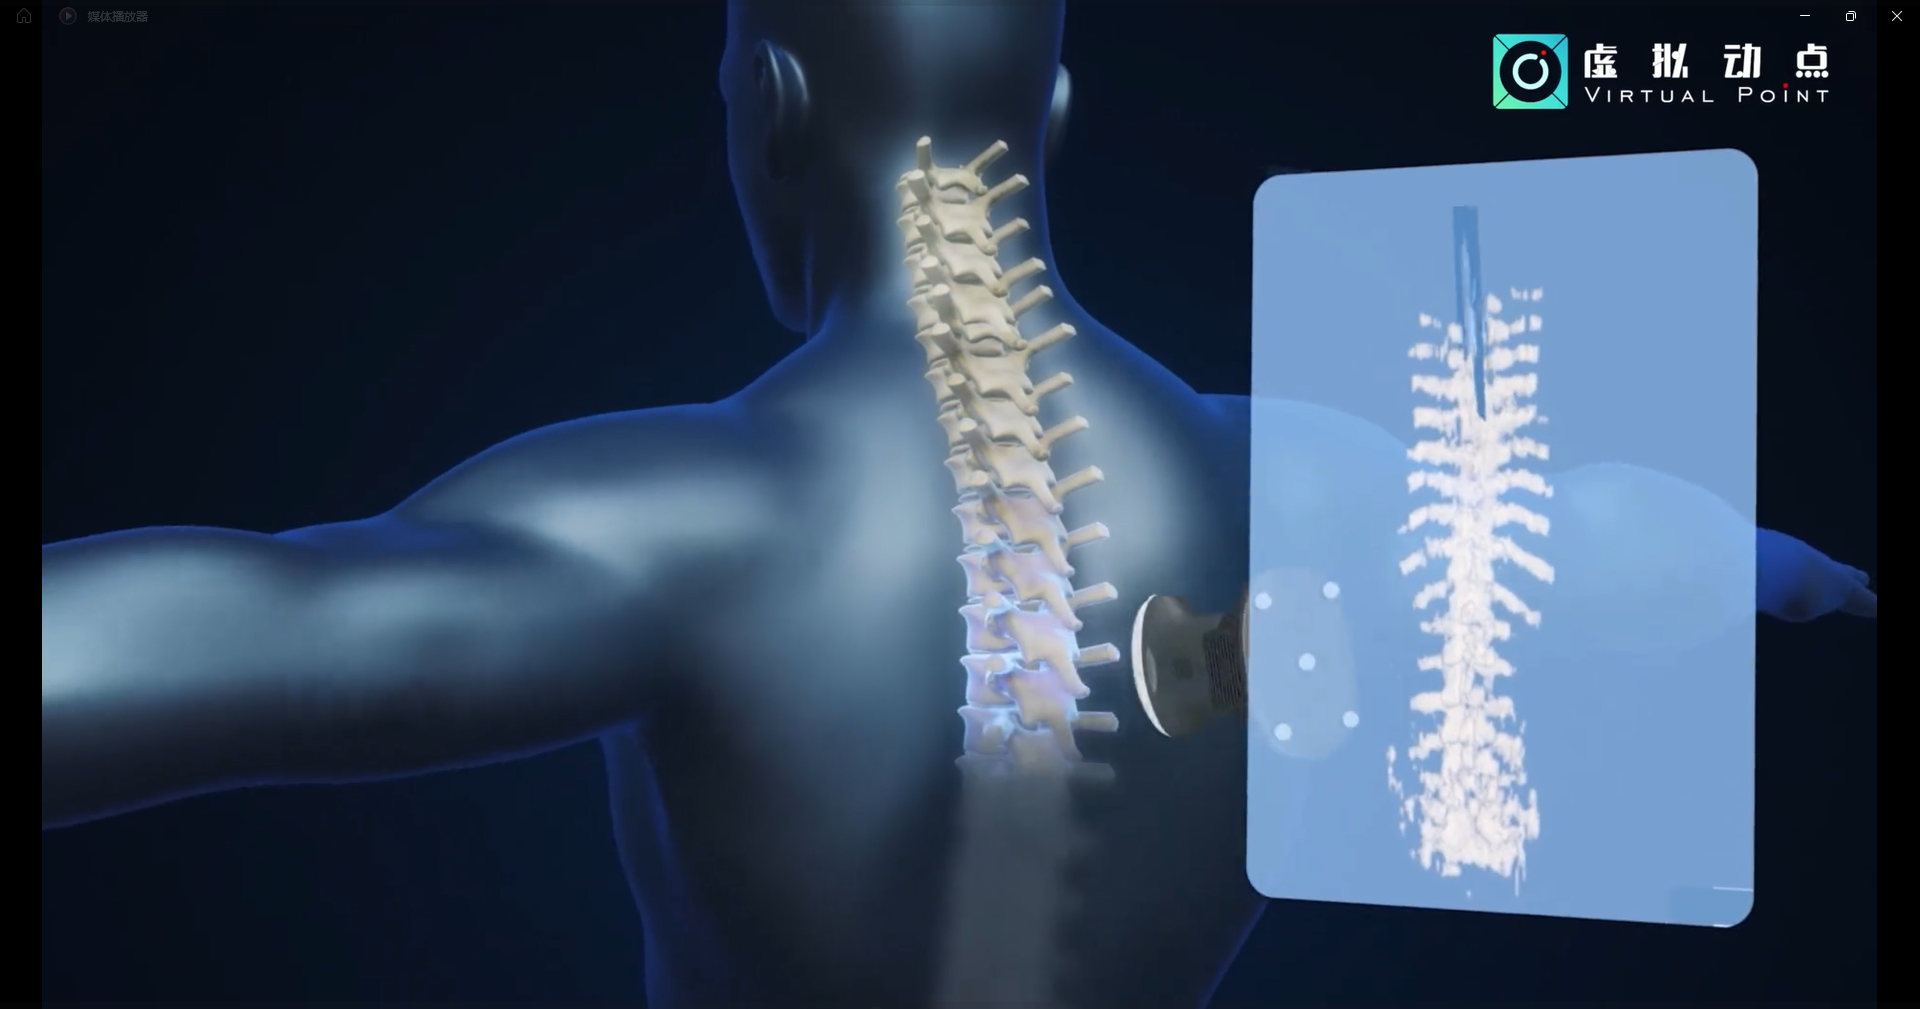

Verdure imaging公司与加拿大金斯顿皇后大学开展了关于脊柱3D超声成像的研究,通过OptiTrack开创了3D超声成像在脊柱诊断中的应用。

以往,因超声波无法有效穿透骨骼,并且容易从探测器反弹,因此使用超声手段无法直接重建3D骨骼。为了探索3D脊柱超声的成像技术,Verdure imaging公司与加拿大金斯顿皇后大学的研究者们将目光投向了“通过追踪技术将2D超声图像增强为更为精准的3D渲染图像”这一思路。最终,在OptiTrack的加持下,他们找到了绝佳方案。Verdure imaging公司 CEO Chris Schlenger表示“星空xingkong探索了各种方式,没有一种能够满足星空xingkong的需求,直到OptiTrack的引入,它可以提供任何星空xingkong需要的跟踪位置,无论是宽角还是窄角、大空间或是小空间、主动或被动等跟踪需求,OptiTrack均可满足。”